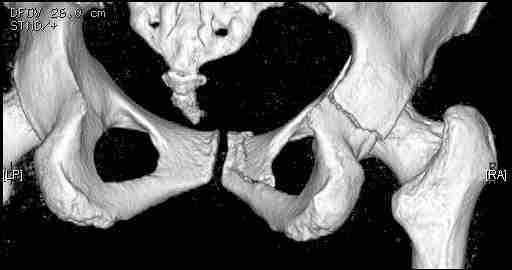

Женщина,58 лет, после ДТП 6 суток. Первично повреждение расценено как переломы ветвей лонной кости. После подтверждения повреждения вертлужной впадины,как чаще всего случается, вопрос встал о тактике. БОльшинство за консерватиное лечение.К сожалению кт у нас "во время" сломался. Прилагаю стандартные снимки вертлужки. У меня следующие вопросы к коллегам:1. Правильно ли рассценивать это повреждение как Т-образный перелом вертлужнй впадины?2. Можно ли добиться анатомической репозиции поверхности вертлужной впадины скелетным вытяжением в данном случае, если нет, что будет этому препятствовать?3. Если смещение останется таким как сейчас, через какое время появится необходимость эндопротезирования (по вашему опыту)?Спасибо.

Уважаемый Коваленко А.Н., снимки плохого качества и нет уверенности, что задняя колонна сломана (смещена). Если кт нет - везите больную в рентгенкабинет (палатником качественные снимки снимки не получатся) и сделайте обзорный снимок таза, Judet и может быть inlet, хуже вы ей не сделаете.

Удалось сегодня вывести пациентку в соседнюю больницу, где есть кт. Срезы сделаны только горизонтальные.

Следом 3d

Приветствую,Антон.Рункова рядом нет,но после полученных данных КТ,обсуждали совместно.Итог обсуждения-развернутый ответ дать не получится,т.к.срезы выбраны не информативные.Если ориентироваться на данные 3D,то ,ИМХО,можно лечить на вытяжении.